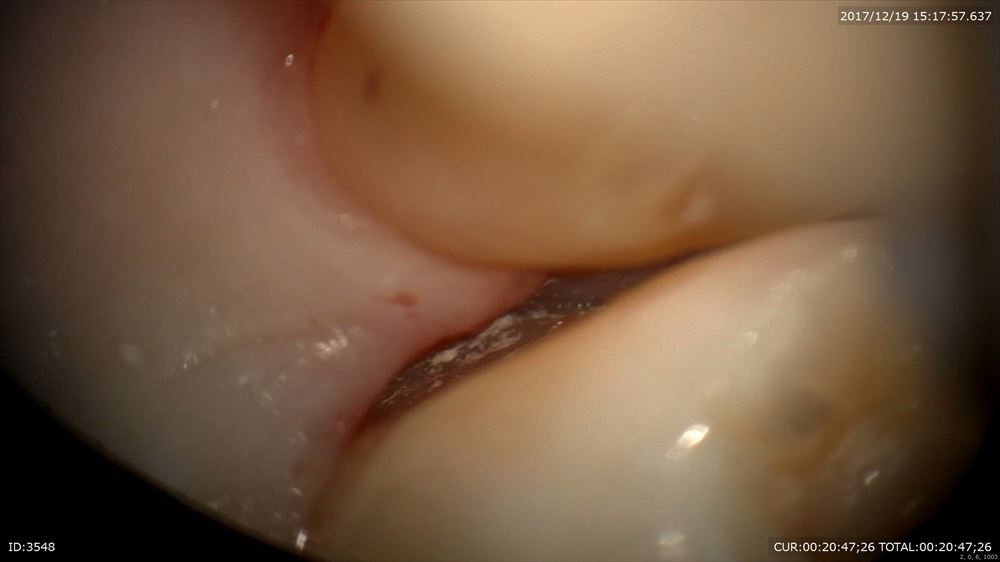

23倍で内視鏡の様にバイオフィルムを無痛で取っていきます。